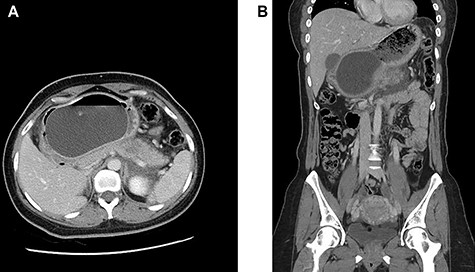

(A and B) Axial and coronal intravenous contrast-enhanced computed tomography images of the abdomen and pelvis showing an IGB compressing the pancreatic body with resultant pancreatic interstitial oedema and peri-pancreatic fluid collection.

Intravenous contrast-enhanced computed tomography of the abdomen, pelvis was done (Fig. 2), and it showed an intra-gastric balloon compressing the pancreatic body with resultant ill-defined hypodensities noted at the pancreatic body and surrounding peri-pancreatic fluid collection suggestive of acute interstitial pancreatitis. No cholelithiasis, intrahepatic or extrahepatic biliary dilatation was seen.

Cross-sectional imaging with contrast enhancement is the modality of choice in assessment of balloon pancreatitis. It usually reveals the presence of a fluid-filled balloon distending the stomach and features of acute interstitial pancreatitis. Most common features of pancreatitis include diffuse enlargement of the gland with peripancreatic inflammation and fat stranding. The mechanism of balloon pancreatitis can be appreciated on computed tomography with the distended balloon causing mechanical pressure on the pancreatic parenchyma and obstructing of the pancreatic duct [3].